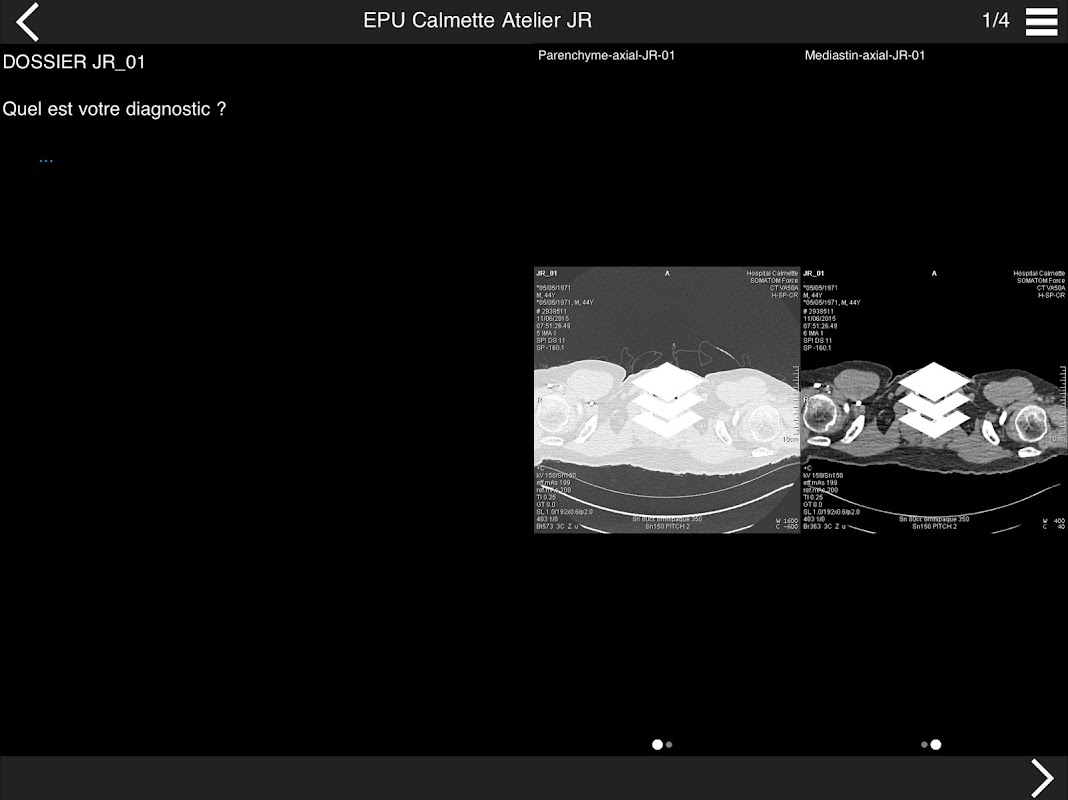

Retrouvez les cas cliniques du Cours intensif de TDM multicoupe du thorax dans cette application.

Thèmes du cours 2017 :

ACTUALISATION DES PROTOCOLES

* BPCO et nodules pulmonaires : recommandations en 2017

* Pathologie interstitielle : lésions élémentaires et « patterns »

* Pathologie vasculaire et médiastinale

* Oncologie thoracique : bilan standard et introduction à l’étude de l’angiogénèse

Pr J. REMY - Pr M. REMY-JARDIN

Dr J.B. FAIVRE - Dr F. PONTANA

Hôpital Calmette - CHRU de LILLE